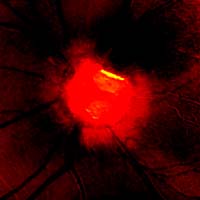

pacientka 1998

(tenze 40-50 torr) Na obrázcích vidíme terče levého oka pacientky, u které se ani opakovanými operacemi nepodařilo snížit nitrooční tlak.

pacientka 2001

Kromě zvětšení a vertikálního protažení exkavace je zřetelné zúžení arterií, zatímco vény jsou zúženy jen méně zřetelně.